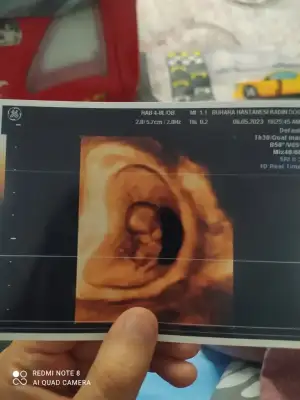

Evet kadın doğum doktoru baktı canım , damar genişlemesi olabilir. Belki bir yara vardı o kanama yapmış olabilir , Corasprin kaynaklı olabilir , üstüne görme olabilir dedi, ama alanda hiç bir kanama görmedi hatta bebişin gelişimi de 3gün ilerde imiş .